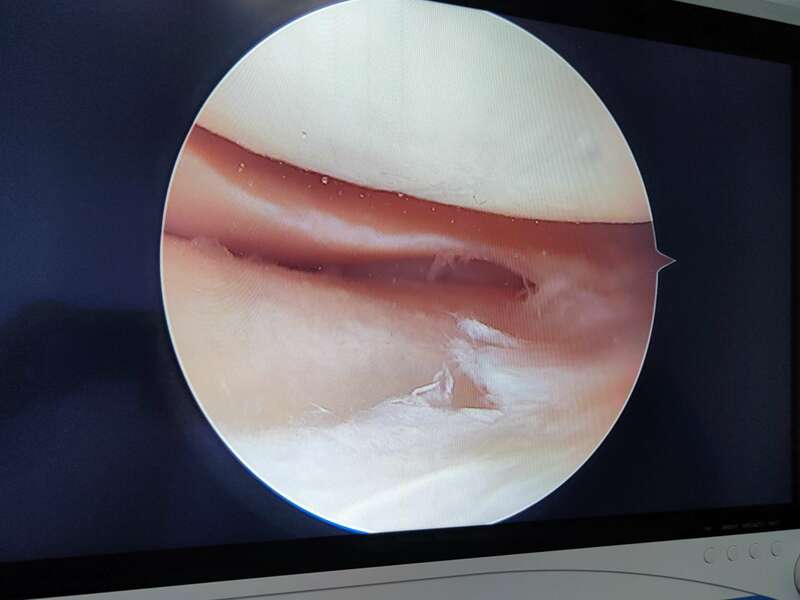

La plupart du temps, les lésions méniscales traumatiques sont traitées chirurgicalement. Deux gestes sont possibles : la réparation méniscale et la méniscectomie. Ces deux interventions sont réalisées au cours d’une arthroscopie et ont des indications spécifiques à chacune.

Nous différencions trois zones. Une « rouge-rouge », au contact de la capsule articulaire (en périphérie), bien vascularisée, qui peut être suturée, surtout chez le jeune. Une zone « rouge-blanche » médiane, qui est moins cicatrisable, car moins bien vascularisé. Et une zone « blanche-blanche » (en profondeur), faiblement vascularisée, et par conséquent rarement suturée.